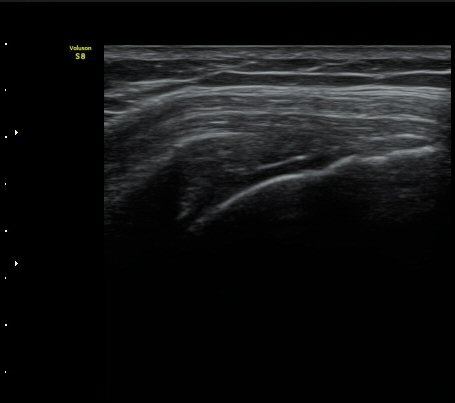

¾î±ú ±Ø»ó°Ç ÃÊÀ½ÆÄ°Ë»ó ±Ø»ó°Ç ºÎÂøºÎ°¡ °üÂûµÇÁö ¾Ê°í ±ÙÀ§ºÎ·Î ´ç°ÜÁ® ÀÖ´Ù(±×¸² 1, 2).

±Ø»ó°Ç Ⱦ´Ü¸é°Ë»ç»ó »ó¿Ï°ñµÎ¸¦ µ¤°í ÀÖ¾î¾ßÇÒ ±Ø»ó°ÇÀÌ º¸ÀÌÁö ¾Ê°í Á¡¾×³¶ÀÌ ÆíÆòÇϰÔ